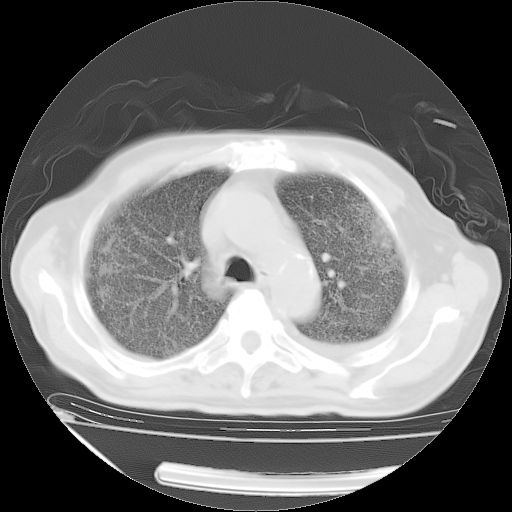

经过24天治疗,岳父的病情基本稳定。生活基本可以自理,可以下床活动。呼吸困难早已消失。体温基本正常。

只是甲强龙用80mg时血小板升到正常,改为60mg后又降到63×10*9/L。

主要治疗甲强龙80mg×14天,60mg×10天;同时抗结核(异烟肼+利福平+乙胺丁醇)。环磷酰胺0.1 tid 10天。

特别感谢胡教授、高管、桃子版主给出关键的治疗建议。桃版把所有肺部影像和全部临床资料请所在医院呼吸科、感染病科、结核科、临床免疫科专家会诊。临床免疫科专家制定了完整的治疗方案。